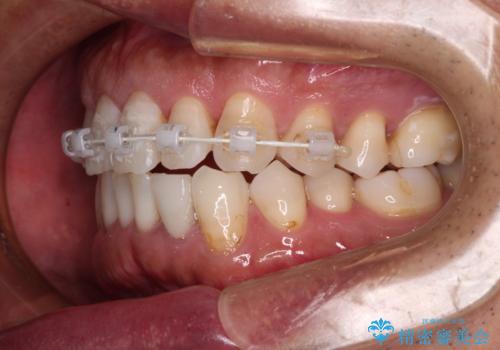

内側にある歯が干渉する 上顎前歯の部分矯正

- 矯正装置

- 審美装置

- 上顎の前歯が内側にあり、下顎のセラミッククラウンと干渉することが気になるとのことで来院された患者様です。

上顎前歯にワイヤー装置を装着し、セラミッククラウンとは干渉しないようにしながら歯列を整えることとしました。

セラミッククラウンとの干渉はすぐに改善され、歯列も整いましたが、一方で、前歯で食事が噛みにくくなり、1年近い治療期間となりました。